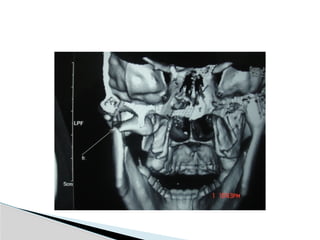

CT

Significant displacement or dislocation,

mechanical obstruction, mult trauma pt, &

intracapsular fracture.

Conventional Radiology At least2 views at right angle to each other. Mandibular series: PA, Lateral oblique or panoramic, & Towne’s view (projects condyle below mastoid process). CT Significant displacement or dislocation, mechanical obstruction, mult trauma pt, & intracapsular fracture. MRI St injuries: effusion, visualization of disc. Imaging